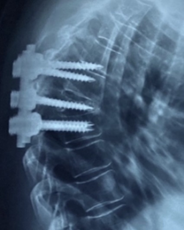

The patient underwent decompression by a posterior approach, and arthrodesis was performed with short instrumentation at T5-T6 (fractured vertebra - instrumented) -T7. The procedure presented some technical difficulty due to atypical bone anatomy with the presence of hypoplastic pedicles. The in-out-in technique was used to position the screws in the pedicles with smaller diameter (Figure 2). The patient progressed well in the immediate postoperative period, and she presented no complaints, no deficits, and good postoperative wound healing after the 3 and 6 month follow-ups. However, radiological control showed fusion failure, worsening of kyphotization, and instrumentation with an anomalous pathway (Figure 3). After analyzing the images, a surgical re-approach with expansion of the levels of arthrodesis was chosen.

Figure 2 Fractured vertebra with slight recoil of posterior wall and demonstrating hypoplastic pedicles.

Figure 3 Kyphotization with instrumentation failure.